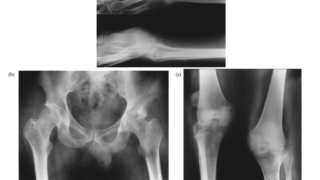

CT値

CTで発見された131例のCT値の中央値は33HU(10-77HU)。

MRI T2高信号

MRIを撮影された43例のうち、22例(52.4%)に認めた。

MIBGシンチグラフィ

98例(65.7%)に術前にMIBGシンチが実施され、92例(94%)に集積を認めたが、6例(6%)はメタネフリン高値かつ病理で確定診断されたがMIBIシンチ陰性であった。

→CT値はやはり10HU以上、MRIのT2高信号は半分程度、MIBGシンチは6%偽陰性。